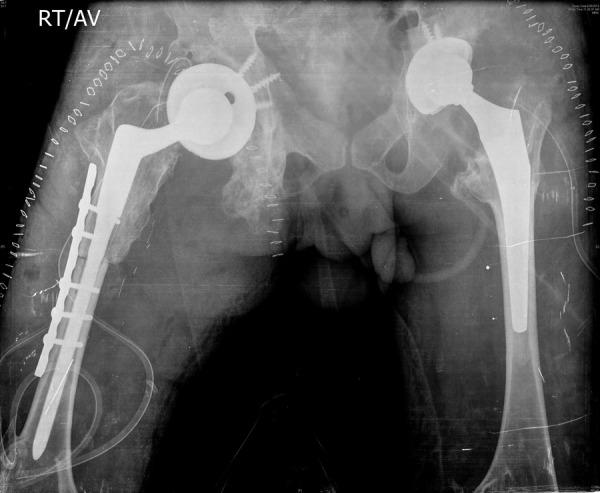

At follow-up, after 12 months both hips were found stable (figure 7), and the osteotomy on the right side had healed. The patient was mobilising with full weight bearing. Harris hip score improved from 15 preoperatively to 78 postoperatively on the right side and 18–86 on the left side.

Figure 7.

Twelve months’ follow-up X-ray of both hips showing well-reduced hips and healed right femoral osteotomy.